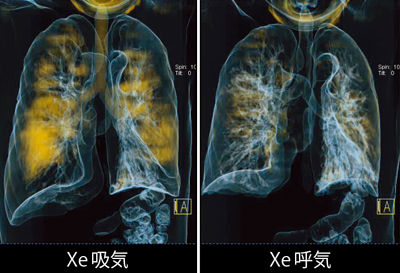

また,最大吸気した後に最大呼気を行ったXeイメージ(図4)では,一見,呼気後のXe残量が少ないため,呼吸機能が保たれているようにも思われる。Xeイメージの残気量で呼吸機能を評価することの妥当性は,今後検討が必要である。

図4 症例1:肺気腫,GOLDU(Xeイメージ)